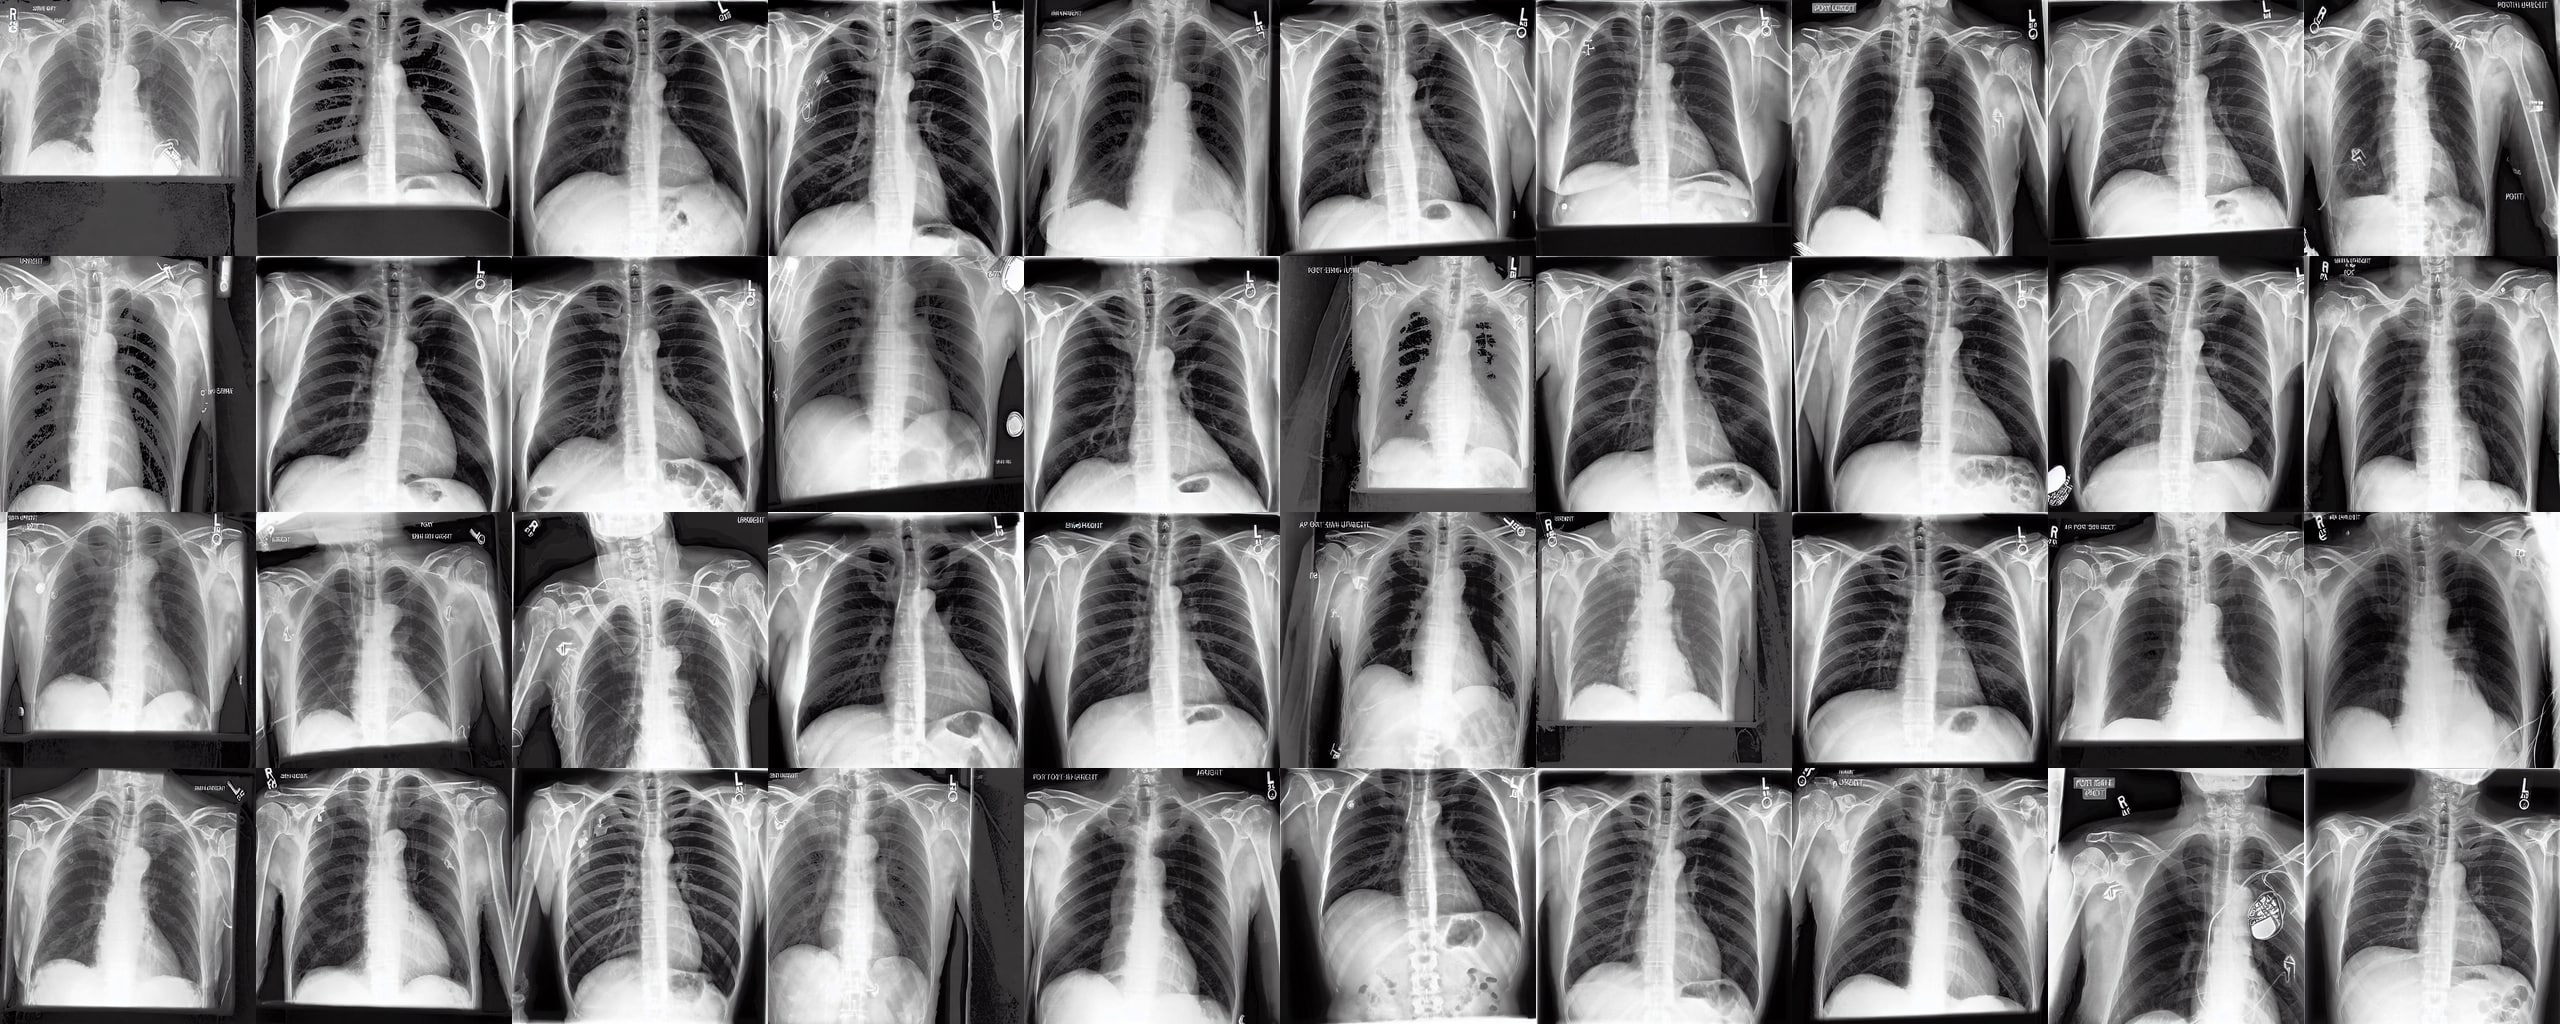

Chest X-rays We use the CheXpert dataset 10.1609/aaai.v33i01.3301590 , which contains 170k training images. This dataset contains diversity in medical devices (such as chest tubes and wires), diseases (such as pneumonia and pleural-effusion) and anatomical details. We implement Rainbow on top of frozen parameters of a finetuned Stable Diffusion v1.5 (SD1.5) by previous work kumar2025prism for chest X-ray data. We generate 2D chest X-ray images based on text prompt conditions, e.g., "Chest X-ray showing Support Devices". In addition to the finetuned SD1.5, we include RadEdit perez2024radedit , a model trained from scratch on multiple chest radiology data such as CheXpert irvin2019chexpert , MIMIC-CXR johnson2019mimic , and NIH-CXR wang2017chestxray data for image editing tasks (more details at Appendix D.3), in the result comparison. Rainbow’s graph generator module includes , , and .

Chest X-rays Figure 4b quantifies generations by Rainbow and baselines using FID and VS. Rainbow achieves a higher VS, indicating greater diversity than the finetuned SD model, while also improving image quality with a lower FID score. Both Rainbow and SD outperform the RadEdit. Figure 6 provides a qualitative comparison, images are generated using the prompt "Chest X-ray showing support devices", where Rainbow generates a more diverse set of medical devices, such as pacemakers, in all generations, while baselines do not show any devices in some images. All models achieve similar CLIP scores of . Additional results including generations, Figure 22 and numeric results, Table 4, are outlined in Appendix E.